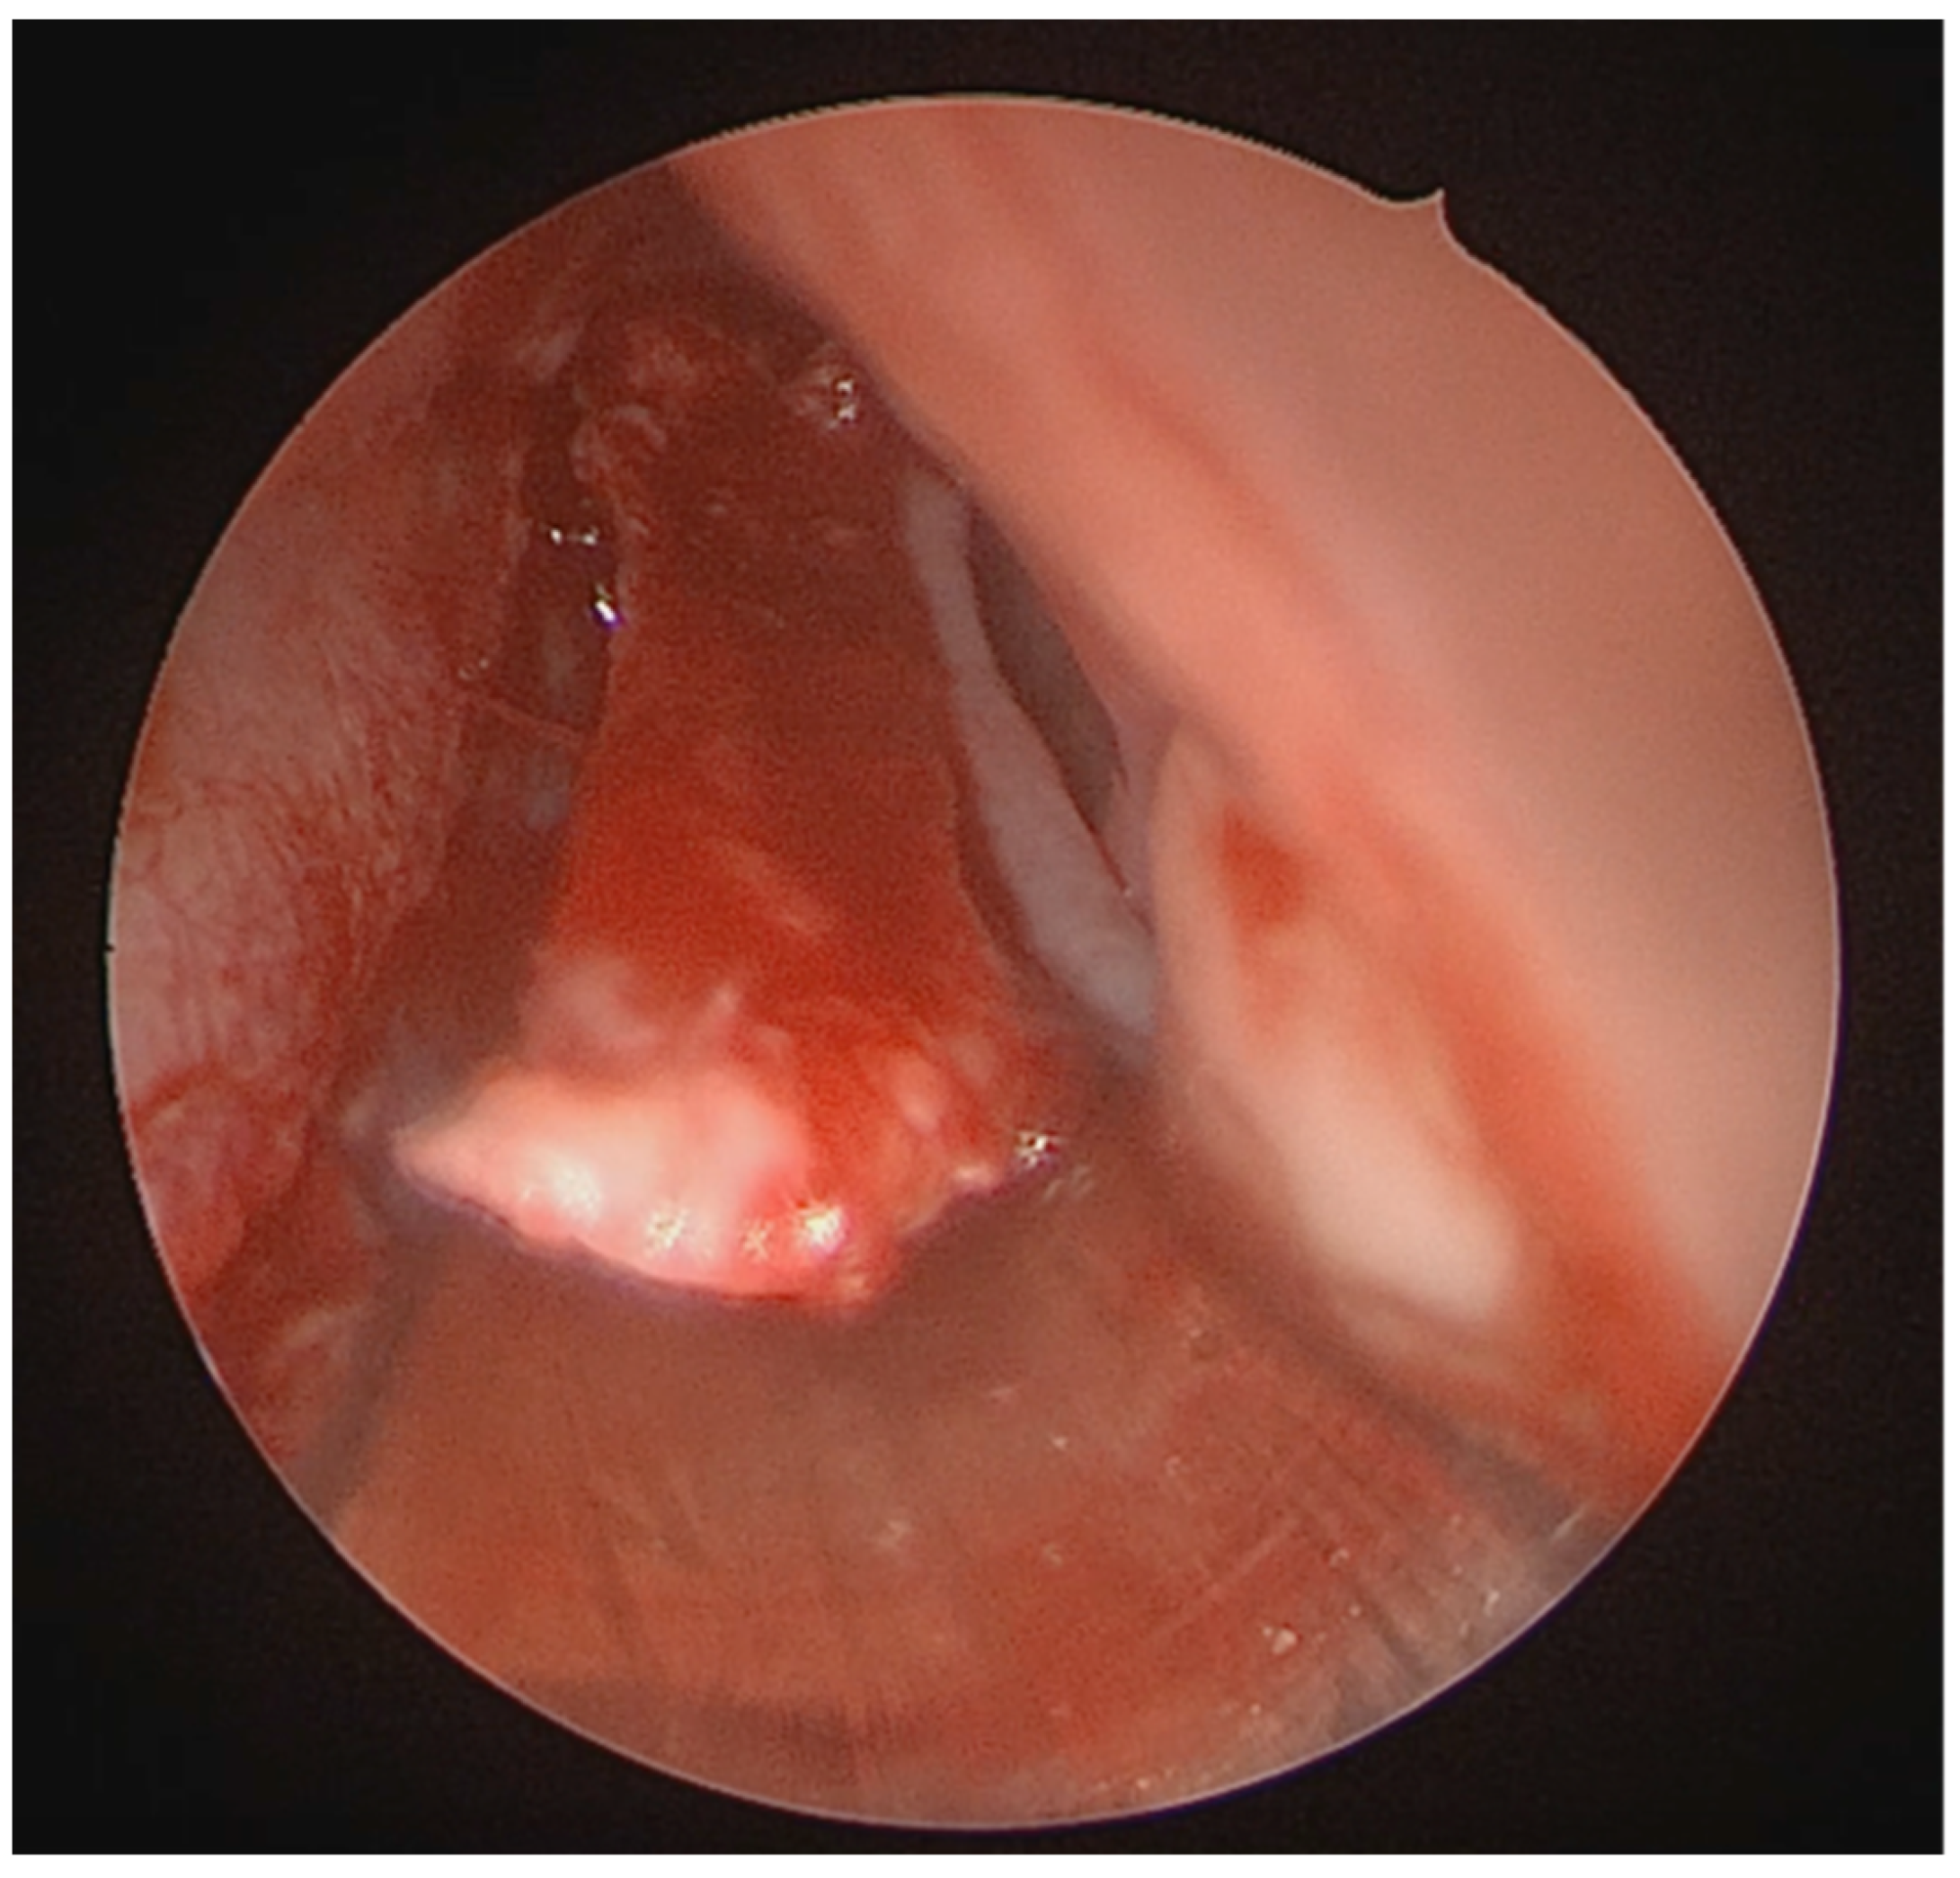

A full-thickness vertical incision was made through the cartilage a few millimeters anterior to the point of maximal deviation, which is typically located at the junction of the quadrangular cartilage and the perpendicular plate of the ethmoid [5]. The contralateral mucoperichondrial flap is then elevated in a similar manner. Once the cartilage and bone were separated from the mucosa, the deviated segments were excised using endoscopic instruments including forceps, Brünings punches, and scissors. The deviated portions of cartilage and bone were excised sharply, and the flaps are subsequently dissected inferiorly down to the nasal floor to correct deflections of the vomer. An osteotome was then positioned at the base of the spur to excise the bony protrusion (Figure 3). Deviated bony segments from the vomer or perpendicular plate of the ethmoid were removed as needed (Figure 4). After complete removal of the spur, the mucoperichondrial flaps were restored to their native positions [15]. When flap apposition was satisfactory, suturing was not required; in such cases, the incision line could be covered with a small segment of Gelfilm. Nasal packing and splints were employed only in selected cases [4].

Figure 3. Osteotome positioned at the base of the spur.

Medicina 62 00135 g003

Figure 4. Resection of the deviated nasal spur using Bruenings septal forceps.